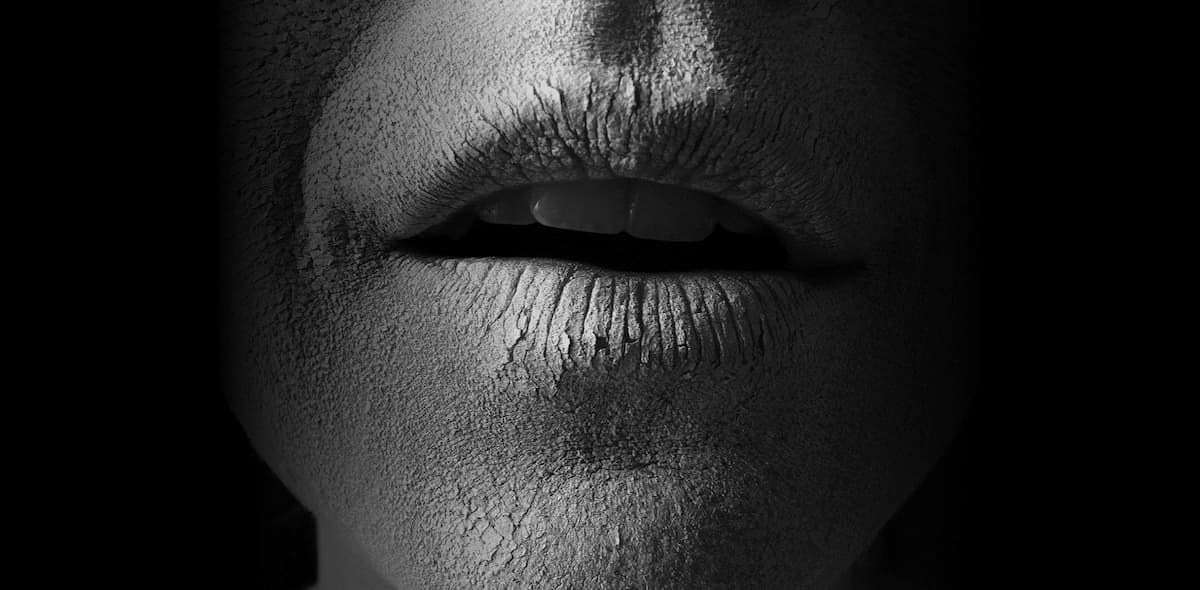

En el ámbito de la odontología y la salud dental, seguro que muchas veces has escuchado lo beneficioso que es el flúor para prevenir las caries y fortalecer el esmalte. No obstante, el abuso y la exposición prolongada al fluoruro pueden causar un problema denominado fluorosis dental. ¿Qué es la fluorosis dental? La fluorosis dental … Leer más